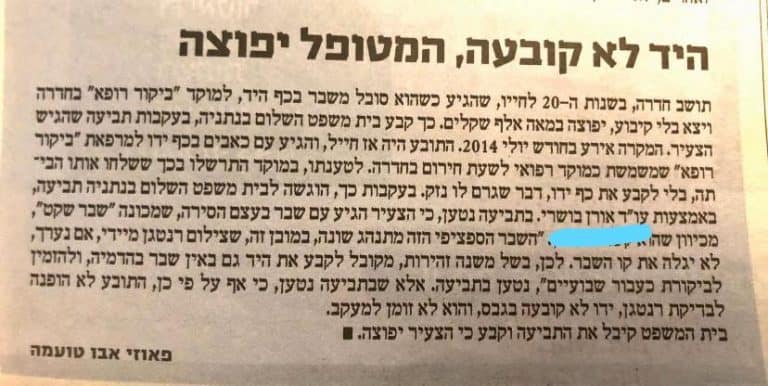

על הרופא לחשוב על שבר גם כשצילום הרנטגן לא מראה פס שבר. זו הפרקטיקה המוכרת. נפיחות בכף היד באזור שורש האגודל רומזת לשבר. מספיק בה כדי לקבע. זו אינה רפואה יוצאת דופן אלא עניין רפואי טריביאלי. למעשה זו אי ידיעה שהיא בגדר רשלנות רפואית. בכל מקרה כזה, וודאי של נזק שהולך ומחמיר, כדאי לפתוח בבירור מדיקו-לגאלי. ראו להלן דוגמא, גזיר עיתון, לפרסום אודות תביעה של המשרד שלנו שהסתיימה גם בפיצוי.